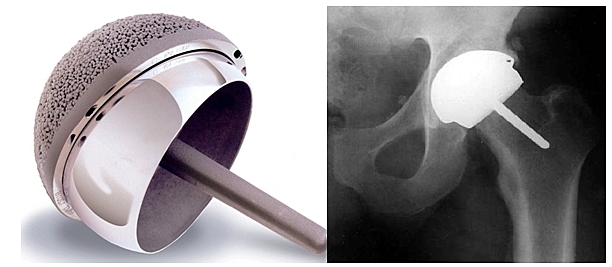

• Prótesis de cadera de recubrimiento

Prótesis de cadera de recubrimiento

Desarrollaron nuevos implantes como las modernas prótesis de recubrimiento, retomando la antigua idea de la prótesis de recubrimiento de Smith-Petersen

• minivástagos femorales

minivástagos femorales

se retomo la antigua idea de la prótesis de recubrimiento de Smith-con la utilización de minivastagos